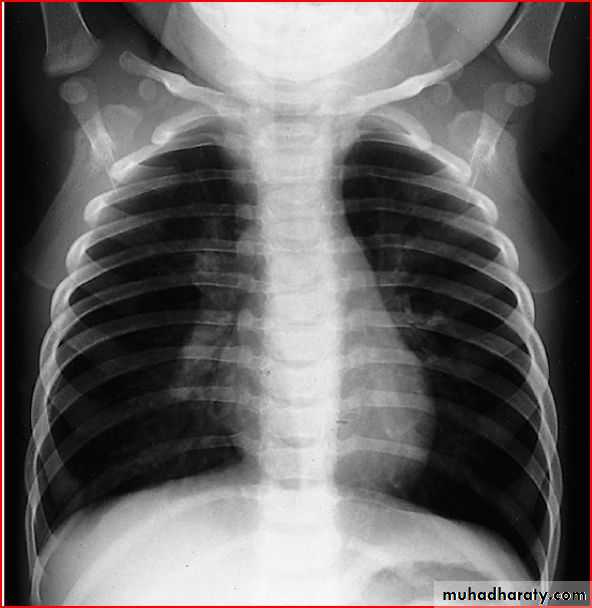

3 month infant presented with cough & dyspnea

Xray shows hyperinflated chest (depresed diaphragm , > 6 ribsMay be bronchiolitis

Hyperinflated chest